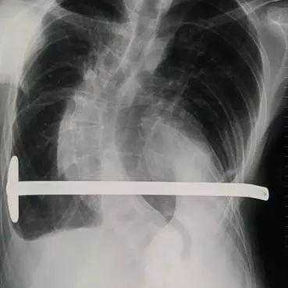

The patient is a 16-year-old male who has been diagnosed with pectus excavatum in childhood but experienced no discomfort in daily life. At the age of 15, he underwent Nuss procedure during which a bar was placed in his chest wall. However, the depression in his chest wall persisted after the surgery, and he even developed new severe deformities. As the deformities gradually worsened, the patient developed scoliosis, and his entire chest wall became completely distorted, eventually losing its basic shape. Later, the patient underwent another minimally invasive surgery for spontaneous pneumothorax, during which the surgeon ligated bilateral pulmonary bullae without treating the chest wall deformities. Ultimately, because of the severe deformities and breathing discomfort, the patient came to our hospital for treatment.

The patient was diagnosed with severe complex chest wall deformities accompanied by scoliosis. The heart was severely compressed and shifted to the left thoracic cavity.